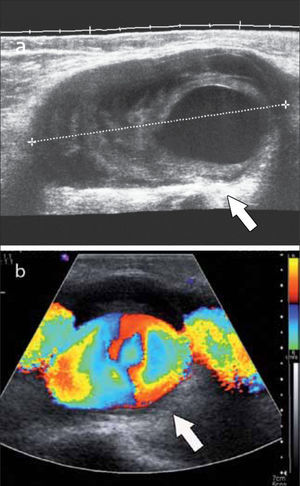

Además con el Doppler Color es posible evaluar la vascularización de las estructuras estudiadas (2).

En el tendón de la porción larga del biceps es útil para estudio de tenosinovitis o luxación. En articulación acromioclavicular podemos encontrar compromiso degenerativo o inflamatorio, derrame, quistes periarticulares o signos indirectos de disyunción. Se visualiza el receso articular glenohumeral posterior en búsqueda de derrame y también los planos musculares periarticulares. La bursitis subacromiodeltoidea se manifiesta como engrosamiento y/o líquido en la bursa (figura 5). La evaluación dinámica permite observar fenómenos de pinzamiento por el ligamento coracoacromial y también pinzamiento subacromial a la bursa o los tendones.